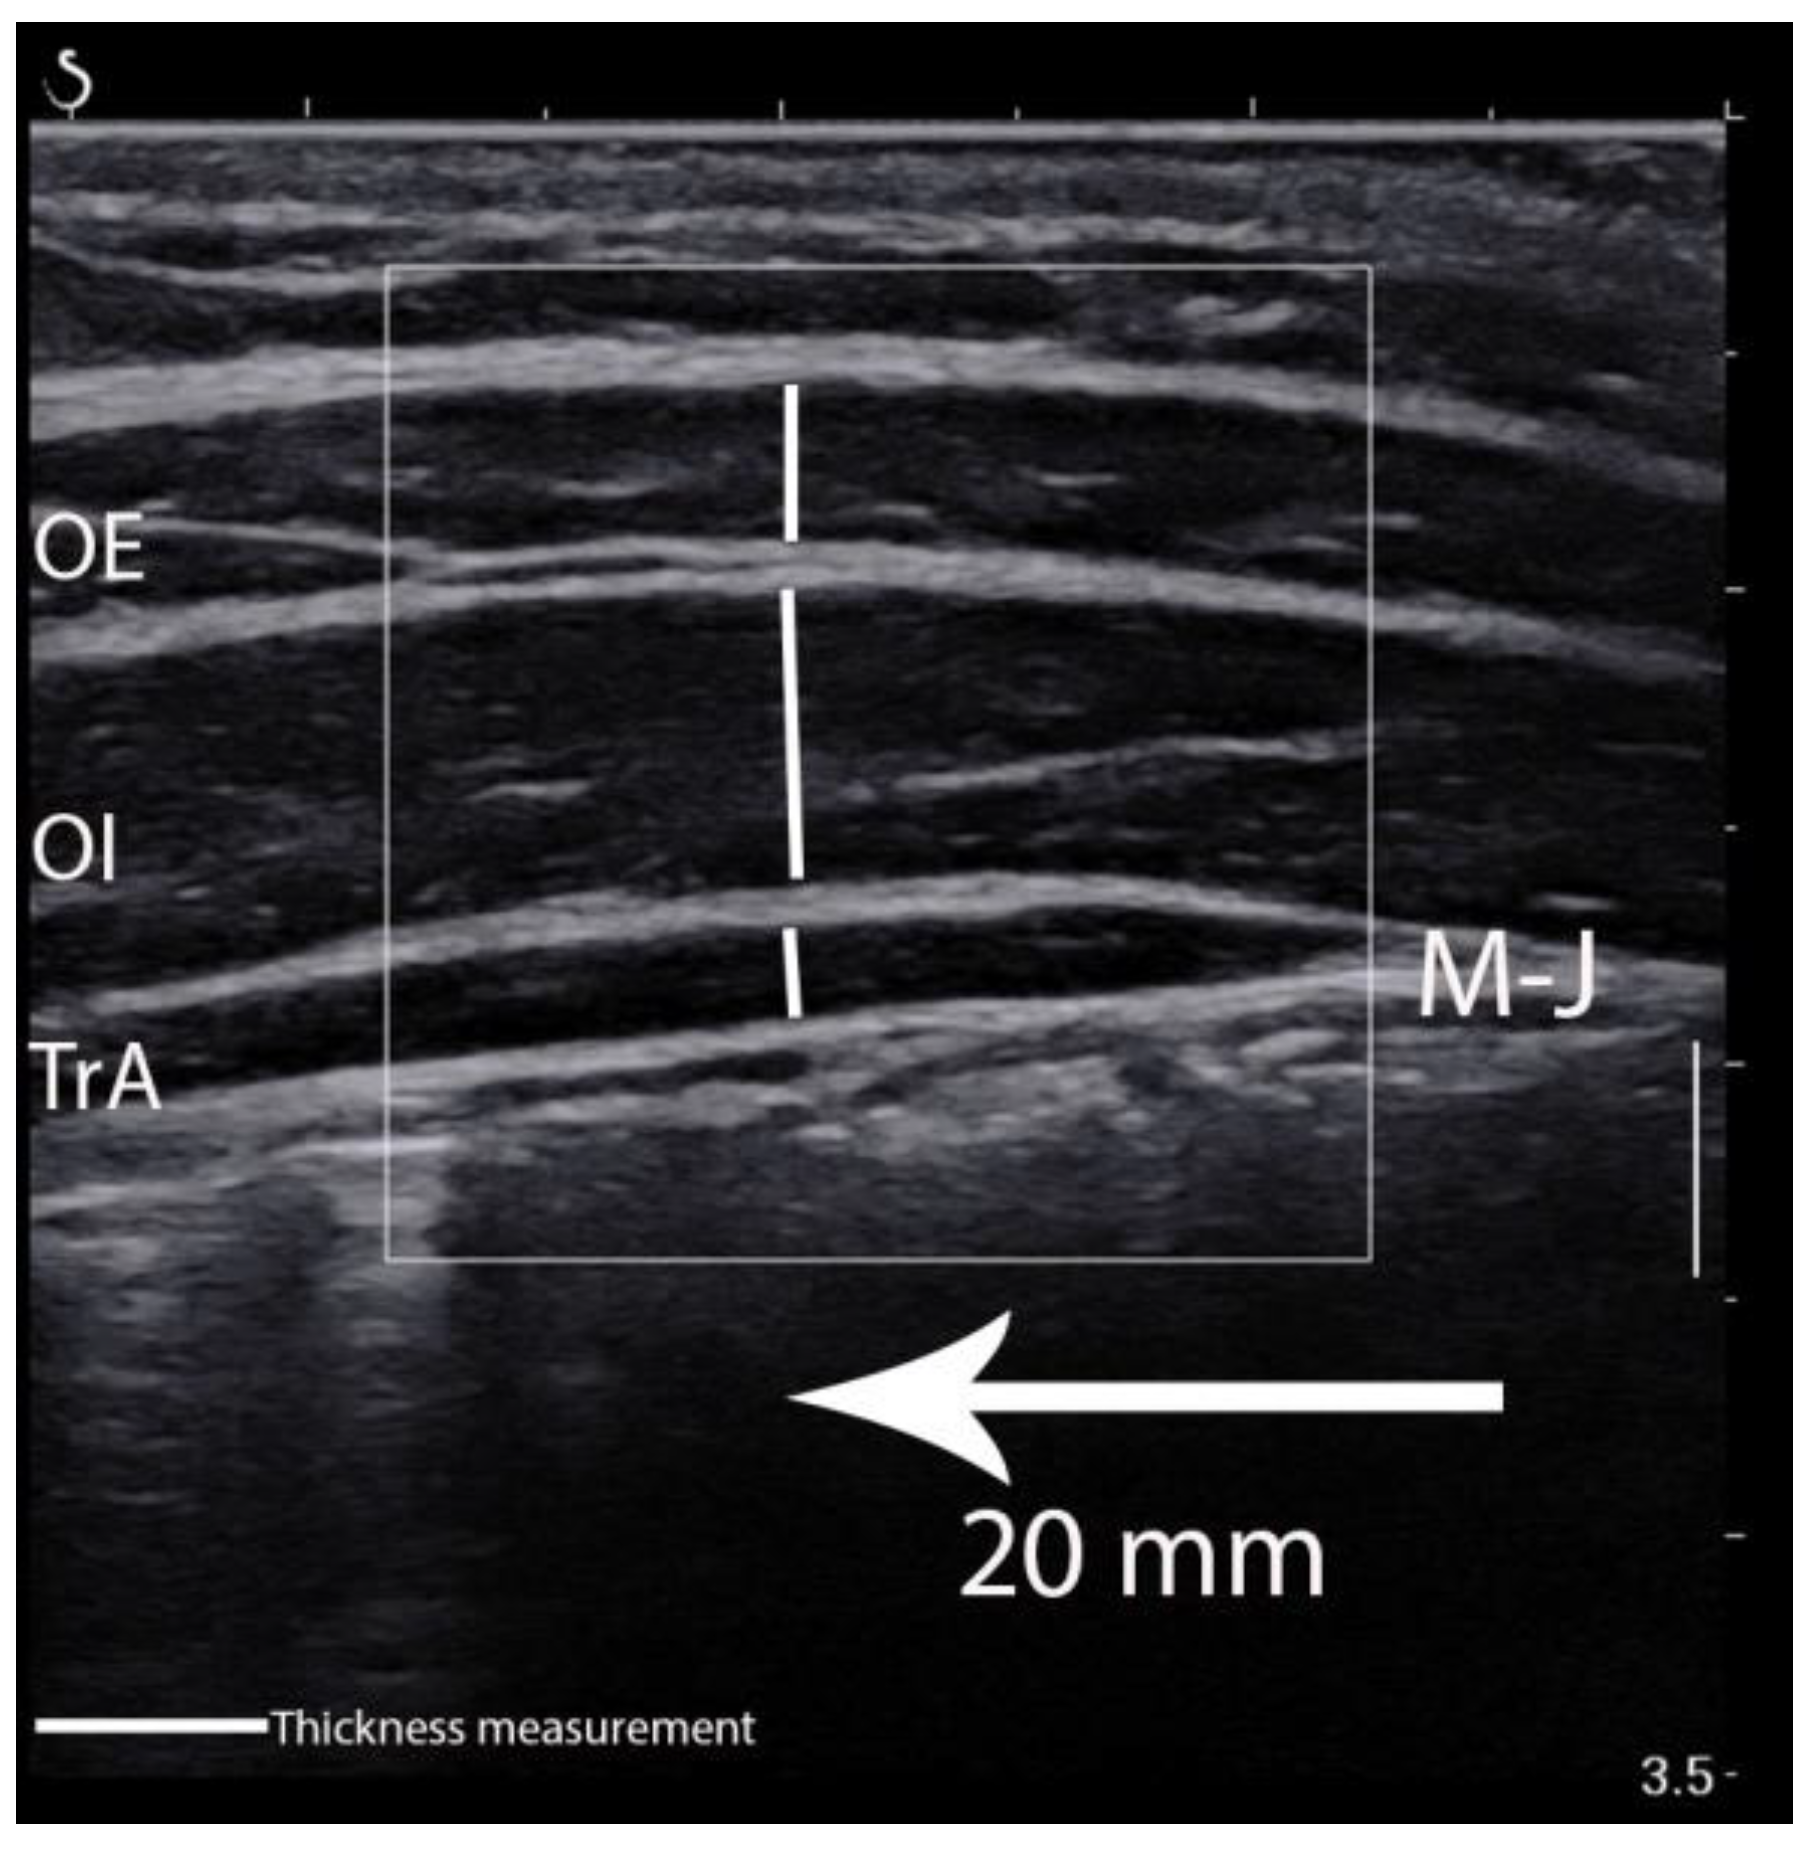

LAMs elasticity was calculated in the ultrasound scanner using the Q-Box quantitative tool after collecting all data (Figure 2). This was used to quantify each muscle shear modulus. Three separate circles were positioned inside the fascial edge of each muscle, and the muscle elasticity within the circle was automatically calculated and depicted in kilopascal (kPa). The mean value of the three separate circles was considered the muscle elasticity value from a given image [16]. In turn, images for LAMs thickness and superficial fat layer measurements were edited and calculated using RadiAnt Dicom Viewer 5.5.1 (Medixant, Poznań, Poland). The edits included enlarging, brightening, and adding contrast. The vertical marking line positioned 20 mm from the musculofascial junction of the TrA was consistently used to re-measure the thickness for each muscle (Figure 3). The vertical distance between the musculofascial layers represented the individual thickness of the oblique external (OE), oblique internal (OI), and TrA [24,30].

Figure 3.

Thickness measurement of the lateral abdominal muscles. OE—oblique external; OI—oblique internal; TrA—transversus abdominis muscle; M-J—myofascial junction of the TrA.